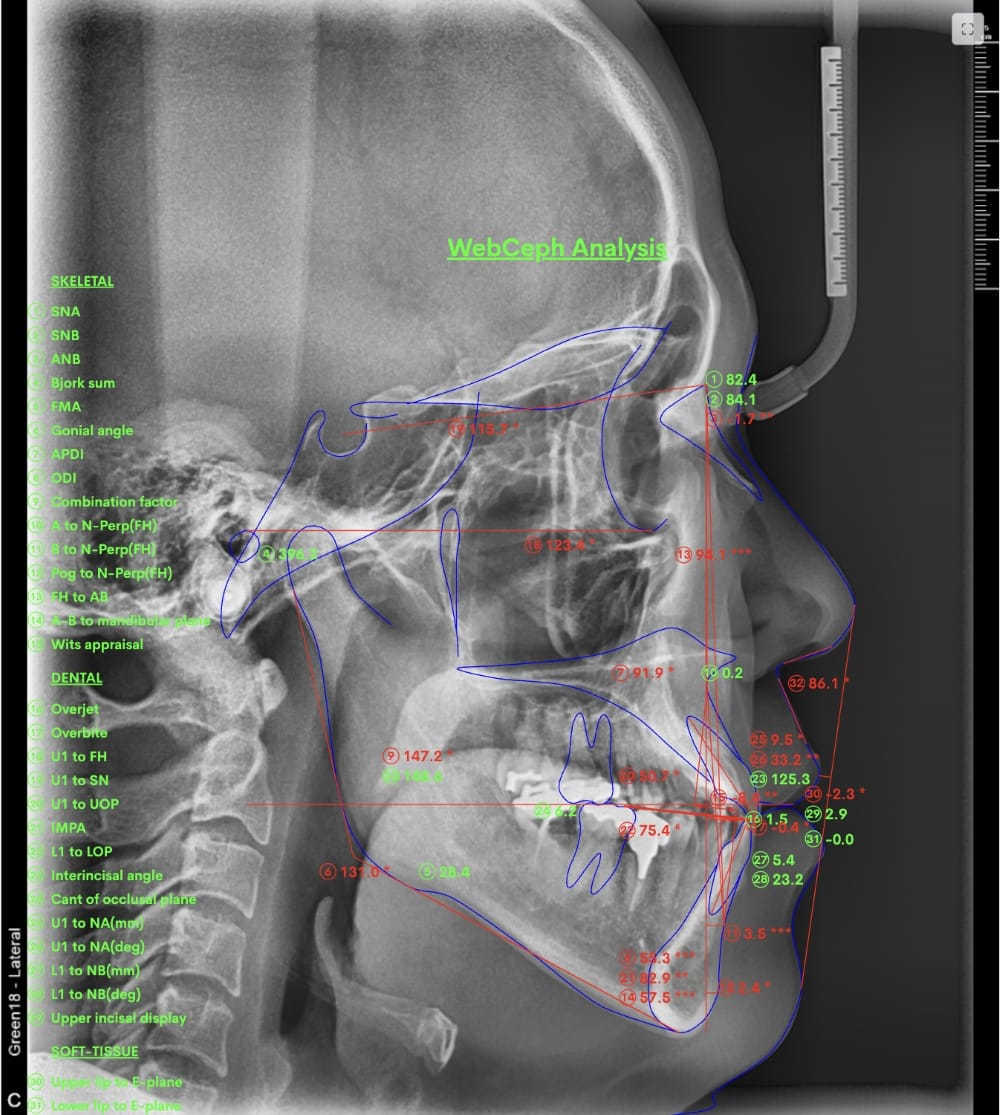

具体的には、口腔内写真やレントゲン写真、特にセファロX線写真を分析し、診断を行います。

例えばセファロX線写真での診断を行い上下の顎の位置のズレが大きいと判断した場合、歯列矯正のみでの治療は困難と判断し、外科的な手術をおすすめする場合もあります。

最後の画像のように奥歯のズレが1本以上あるケースでは、歯列矯正のみでの受け口の改善は困難と判断することが多いです。

分析をしますと

- 骨格的な上下あごの前後差は中等度

- 噛み合わせの位置も下あごの奥歯が半分くらい前にズレていた

- 上の前歯が前に傾斜、下の前歯が内側に傾斜しているにもかかわらず、受け口

というケースで、外科的な処置も検討するようなケースでした。